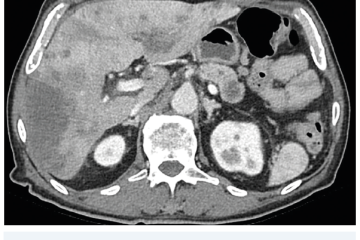

Několik studií se zabývalo AI asistovanou CT detekcí karcinomu pankreatu s AUC 0,79–0,99 %,6–8 tedy přesností porovnatelnou s přesností práce zkušeného radiologa. Stran časné detekce proběhla studie posuzující přesnost AI modelu v detekci karcinomu pankreatu v období 3–36 měsíců před prvními projevy onemocnění. Zařazeno bylo 155 pacientů s karcinomem pankreatu a 265 zdravých kontrol. AI model zde dosáhl AUC 0,98, což výrazně předčilo radiology, kteří při popisování stejných případů dosáhli AUC 0,66.9 Studie využívající DL model pro rozlišení zdravé slinivky od nálezu pankreatických neoplazií, tedy karcinomu pankreatu, intraduktální papilární mucinózní neoplazie (IPMN), serózních a mucinózních cystických neoplazií a solidní pseudopapilární neoplazie, byla prezentována s AUC 0,91, tedy opět odpovídající přesnosti popisu radiologa.10 Pro další vývoj a možné klinické využití bude potřeba přístupu k rozsáhlému archivu CT snímků karcinomu pankreatu, aby se ML modely mohly zdokonalovat. Další studie se věnovaly AI asistované diferenciální diagnostice. Ta bývá u lézí pankreatu velmi obtížná a pokrok v této problematice je tak velmi přínosný. Mezi nejzajímavější patří studie zabývající se rozlišením serózních a mucinózních cystadenomů s AUC 0,932.11 Další studie zkoumala úspěšnost rozlišení karcinomu pankreatu od zbytnění pankreatu při určitých formách chronické pankreatitidy (MFP – mass forming pancreatitis) s AUC 0,866.12 V další studii byla AI využita k rozlišení fokální autoimunitní pankreatitidy od karcinomu pankreatu s AUC 0,97.13 V rámci MR proběhlo několik studií, které se zaměřily na AI asistované zachycení a klasifikaci pankreatického karcinomu či IPMN. Studie klasifikující IPMN pomocí konvoluční neuronové sítě (CNN – convolutional neural network) byla schopna rozlišit dysplazii vysokého stupně od přítomnosti karcinomu se senzitivitou 76 %, specificitou 78 % a AUC 0,78.14 Další studie porovnávala AI modely CT a MR v predikci maligního IPMN. Výsledky ukázaly, že MR model s AUC 0,94 byl přesnější než CT model s AUC 0,864.15 S využitím PET/CT byl prozkoumán AI model rozlišující od sebe akutní pankreatitidu a karcinom pankreatu s AUC 0,9668.16 Výsledky AI v oblastech zobrazovacích metod jsou tak slibné. Dosahují minimálně přesnosti srovnatelné s radiologem a zejména v problematice časných karcinomů pankreatu člověka svojí přesností převyšují (obr. 1–5).

EUS umožňuje přesné vyšetření pankreatu. Lze také identifikovat a vyšetřit regionální lymfatické uzliny a vztah pankreatických lézí k okolním cévním strukturám. EUS může také sloužit jako navigace k odběru bioptického materiálu k cytologickému a histologickému vyšetření.21 AI je zde využívána k potvrzení malignity v IPMN. Kuwahara a kol. dosáhli s využitím 3 970 snímků a CNN algoritmu velké úspěšnosti v diferenciaci benigní a maligní IPMN s AUC 0,98.22 Řada studií se již zabývala AI asistovaným rozlišením chronické pankreatitidy a karcinomu pankreatu s AUC 0,940–0,986.23,24 Velká studie obsahující 1 174 461 snímků z celkem 583 případů hodnotící rozlišení autoimunitní pankreatitidy, karcinomu pankreatu, chronické pankreatitidy a normálního pankreatu dosáhla pro karcinom pankreatu AUC 0,97625 (obr. 6–9).